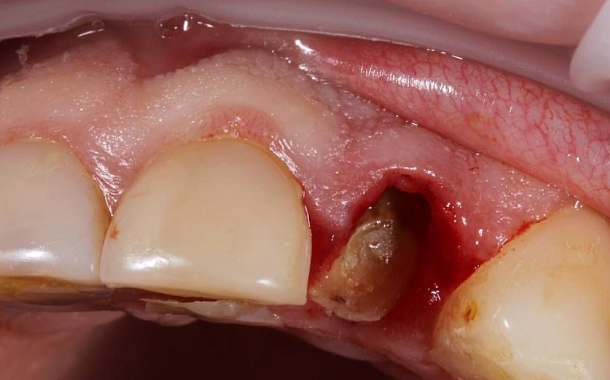

Применение Indiba после стоматологических процедур, таких как удаление зубов, костная пластика и имплантация, обеспечивает ряд значительных преимуществ:

- Ускоренное заживление: за счет стимуляции клеточной активности способствует более быстрому восстановлению тканей.

- Уменьшение отека и боли: улучшение микроциркуляции помогает снизить послеоперационный отек и болевые ощущения.

- Профилактика осложнений: активизация иммунных процессов снижает риск развития инфекций.